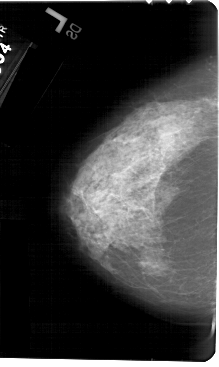

A_1511_1.LEFT_MLO

LEFT_MLO LINES 5491 PIXELS_PER_LINE 3376 BITS_PER_PIXEL 12 RESOLUTION 43.5 NON_OVERLAY